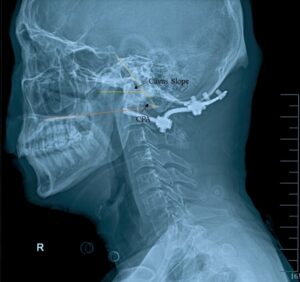

Fig.1 Clivopalate angle (CPA) and Clivus slope

Second, another study conducted by Baysal B et al [3] showed that the diagnostic accuracy of CPA was the lowest (0.438) compared with other angles. They thought that CPA was inadequate for the diagnosis of BI. According to Ma et al, the diagnostic accuracy of CPA, CXA or CDA (0.973, 0.964) were higher than that of CXA and CDA alone (0.957). But the increased diagnostic ability was probably due to the combination of angles and the added value was quietly limited. We boldly assume that the diagnostic efficacy of CPA is not as good as that of clivus slope, which is formed at the intersection of the Wackenheim line and a horizonal line. Clivus slope is simpler and easier to measure than CPA, and can be adjusted during surgery.